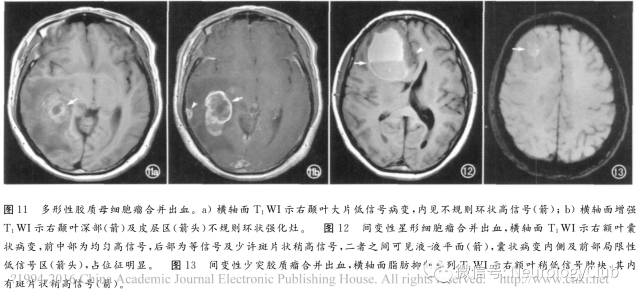

1. 原发脑肿瘤

①垂体瘤:囊变、出血、坏死常见于10mm以上者,急性出血可导致肿瘤快速增大及压迫视交叉和垂体其余部分,出现急性视力下降及内分泌功能异常,并伴头痛,称垂体卒中,溴隐亭治疗者出血发生率增加;亚急性期MRI表现为T1WI高信号,脂肪抑制无信号下降(图10),随访可见病变缩小及囊腔形成。主要应与Rathke裂囊肿及颅咽管瘤鉴别。②胶质瘤:间变性星形细胞瘤、多形性胶质母细胞瘤(图11、12)和少突胶质瘤(图13)易出血,尤其是镜下可见的出血。③其它肿瘤如淋巴瘤(图14)、室管膜瘤(图15)与室管膜下瘤、髓母细胞瘤(图16)、血管母细胞瘤(图17)、原始神经外胚层肿瘤(图18)、表皮样囊肿及神经源性肿瘤,甚至少数脑膜瘤(图19)也可继发出血,形成瘤内T1WI高信号、甚至囊液-血液平面。